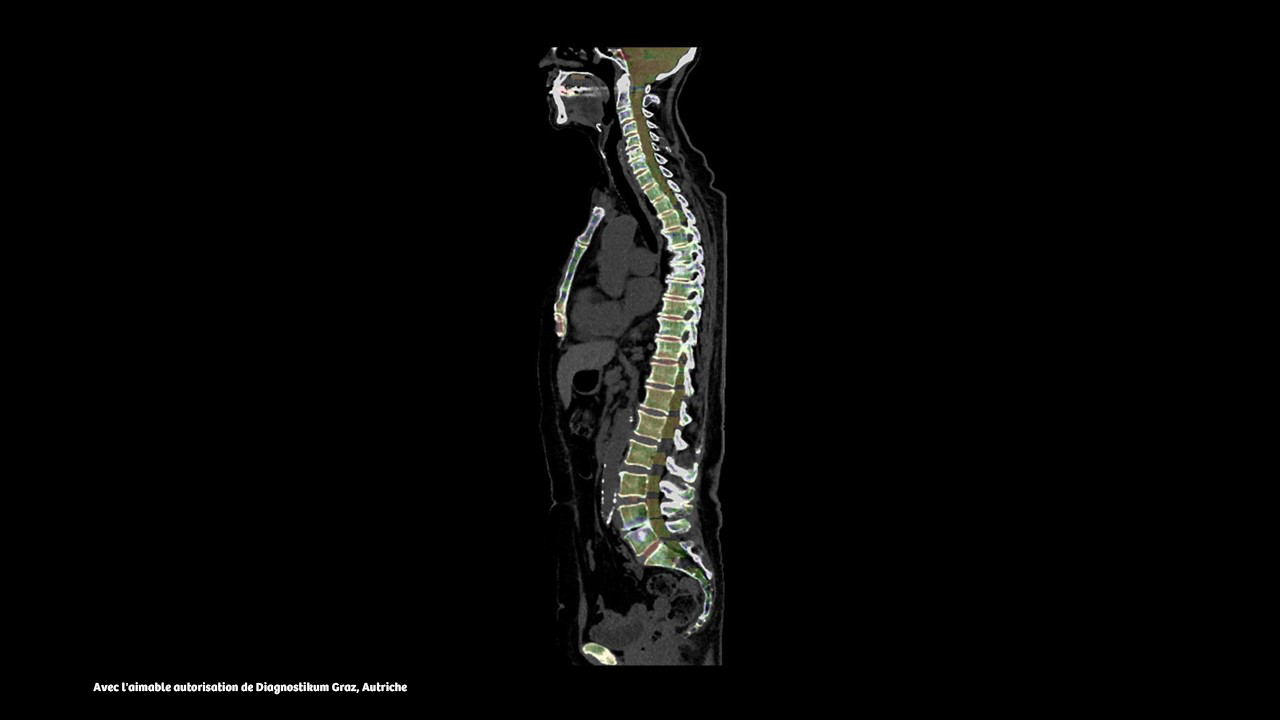

La résolution spatiale ultra-élevée du NAEOTOM Alpha.Pro permet une meilleure évaluation diagnostique des vaisseaux coronaires qu’avec un scanner conventionnel avec une dose de rayonnement modérée. La résolution temporelle de Dual Source fournit des informations uniques sur les valves cardiaques.

La vitesse Dual Source du NAEOTOM Alpha.Pro permet d'obtenir des temps d'acquisitions si courts que le cœur peut être visualisé entre deux battements cardiaques. L'imagerie Quantum Spectrale fournit des informations supplémentaires en une seule acquisition.

La technologie Quantum HD Cardiac a une résolution temporelle maximale de 66 ms permettant une évaluation précise des patients atteints de calcifications coronaires sévères.